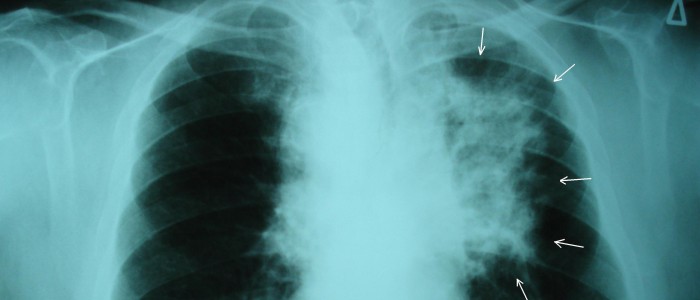

Щоб вивчити потенційний вплив препарату, дослідники зареєстрували приблизно 682 пацієнти з недрібноклітинним раком легень (недрібноклітинний рак є найбільш поширеною формою захворювання легень) з 26 країн світу, все віком від 30 до 86 років. років. З цих сотень пацієнтів 339 випадково отримали таблетки осимертинібу виробництва компанії «АстраЗенека», а 343 — плацебо.

Важливо відзначити, що, як зазначає The Guardian, у всіх учасників дослідження був мутантний ген EFGR, мутація, яка присутня приблизно у чверті випадків раку легенів у всьому світі. Він також має тенденцію бути присутнім у хворих на рак легенів, які ніколи не курили або рідко курили, а також частіше зустрічається у жінок, ніж у чоловіків. Крім того, за даними The Guardian, близько двох третин пацієнтів із раком легень, які взяли участь в успішному випробуванні, становили жінки.